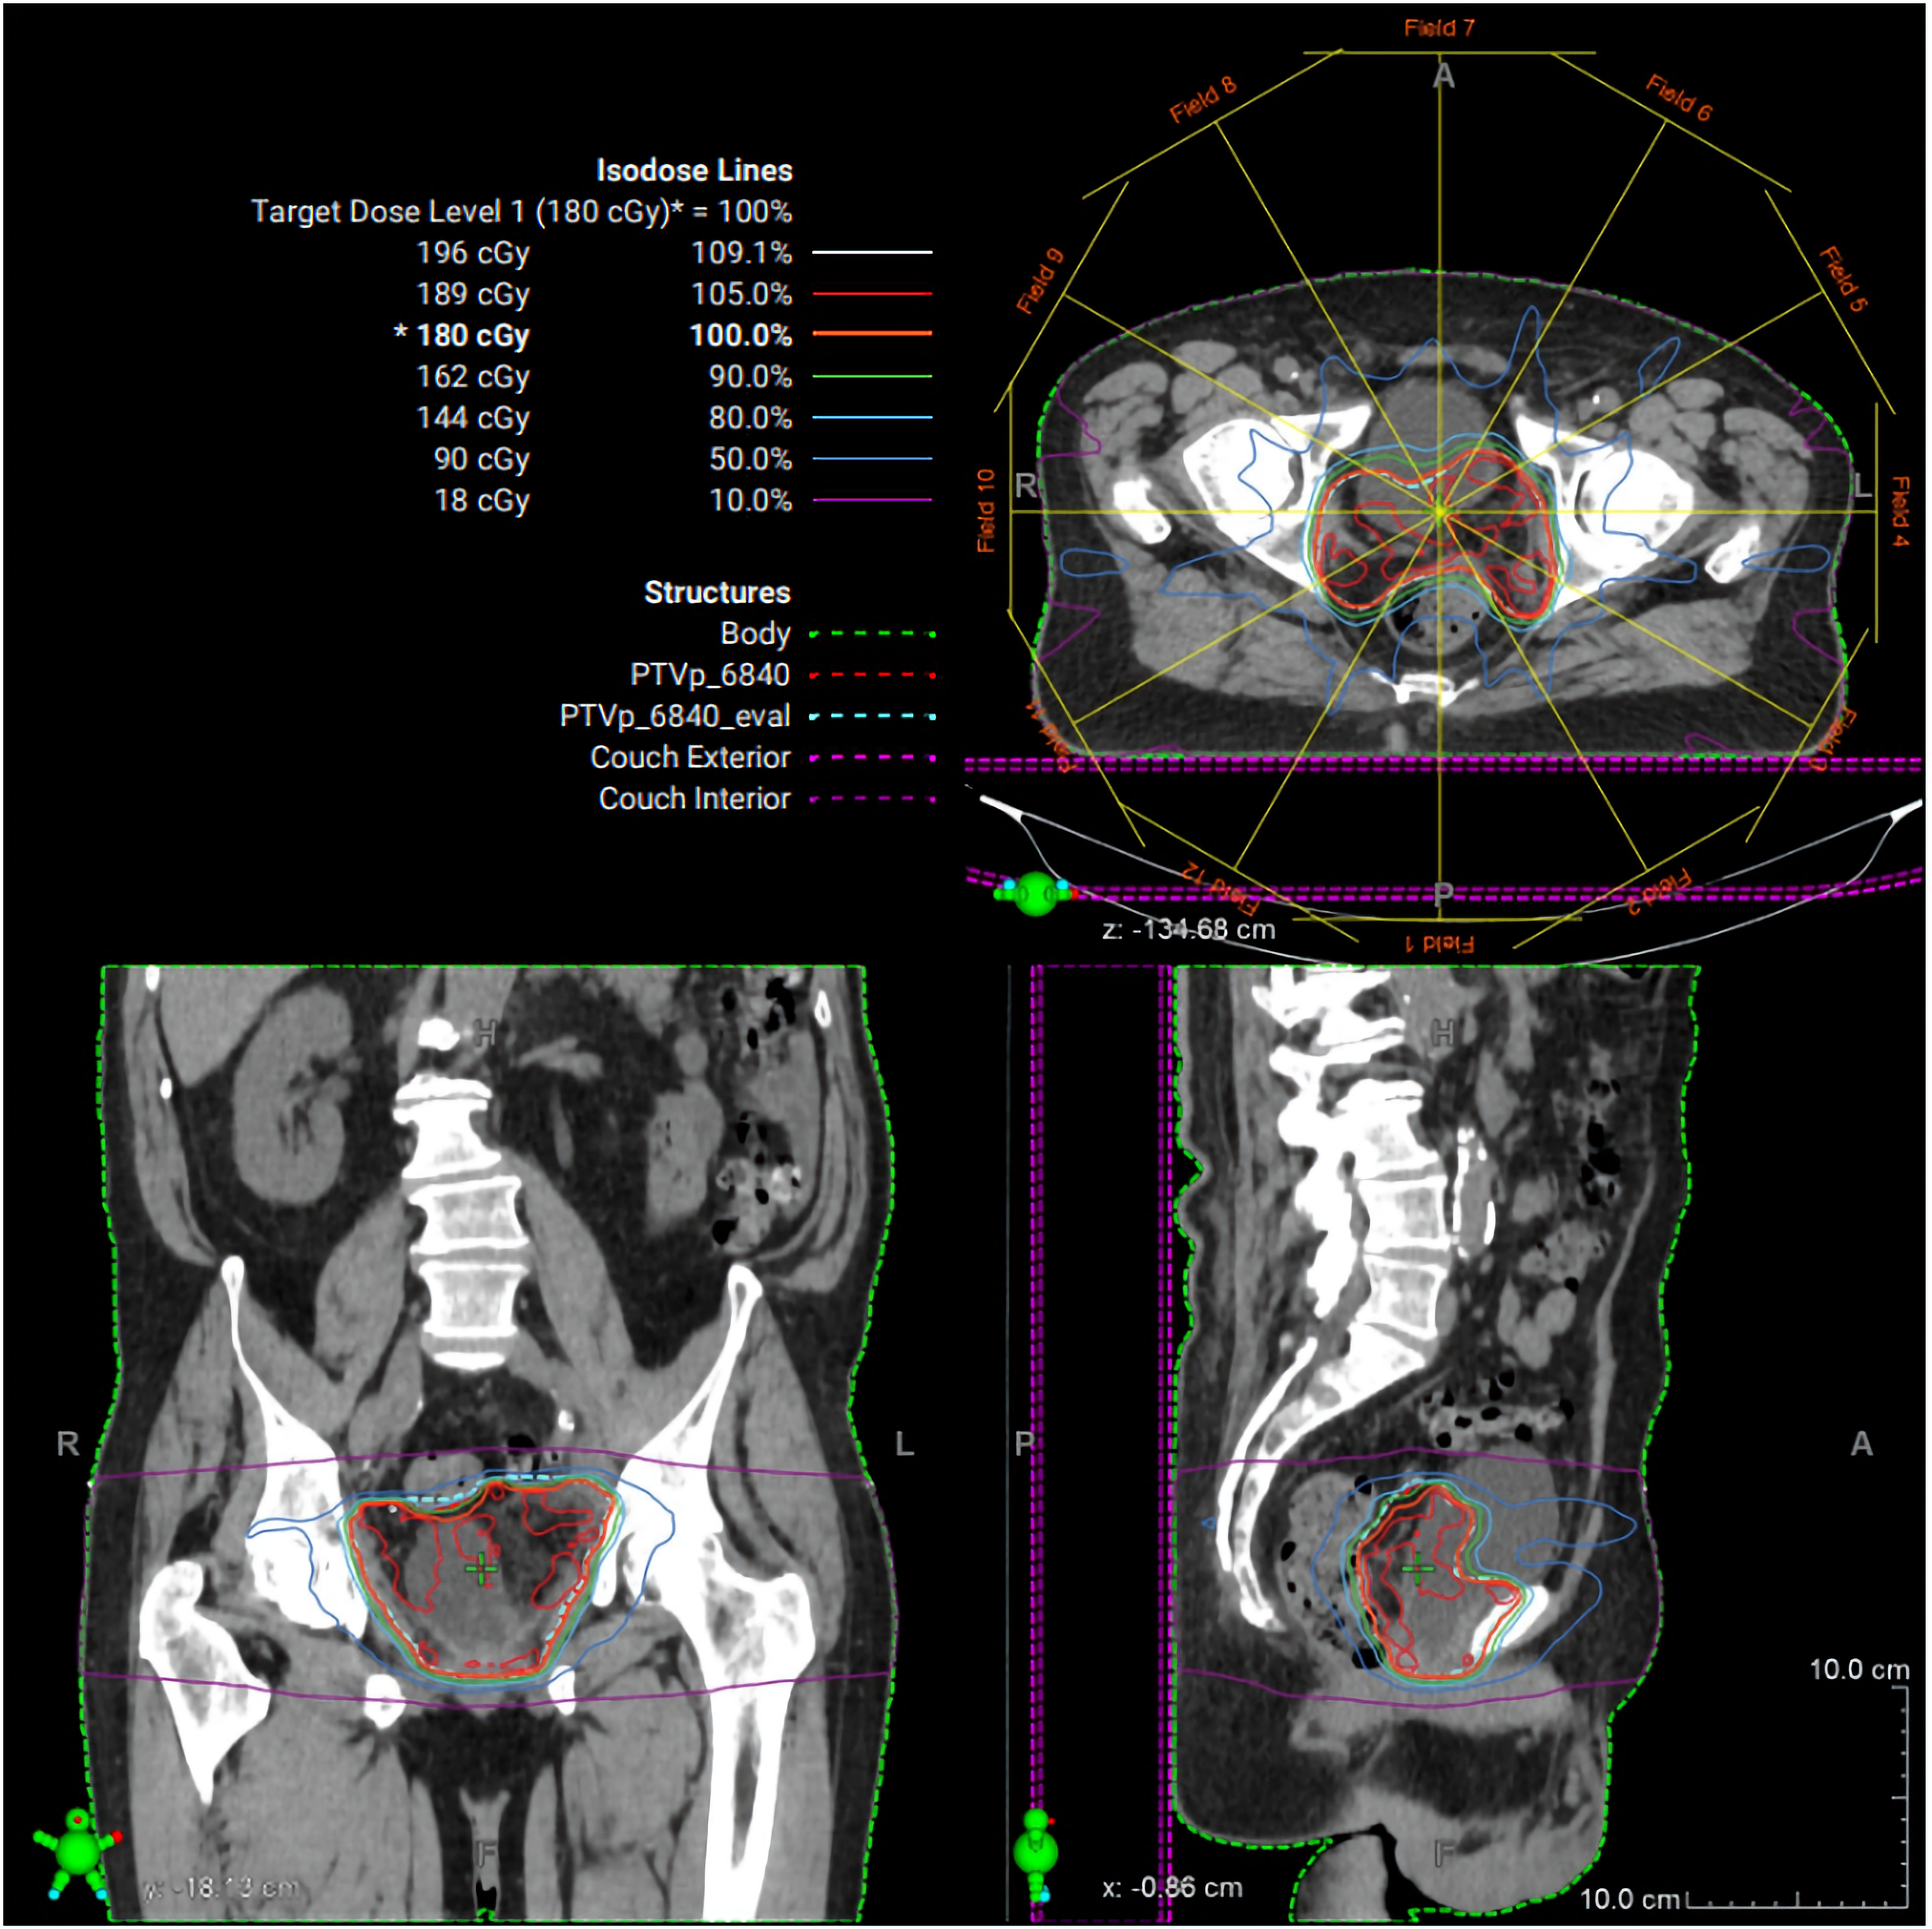

Postoperatively, PSA remained undetectable; however, the extensive SV mass prompted additional biomarker surveillance, and ctDNA (Signatera®, Natera, Inc., Austin, TX, USA) testing was elected. Two months later, ctDNA was positive for minimal residual disease. Adjuvant radiation therapy (RT) to the postoperative bed was administered based on high-risk features of the PSVA, including tumor extent and margin status, using intensity modulated RT to 68.4 Gy in 38 fractions with daily image guidance (Fig. 4). Given undetectable PSA and lack of high-risk pathologic features of the synchronous prostate cancer, androgen deprivation therapy was not delivered concurrently with RT. Following RT, the patient’s ctDNA converted to negative (Fig. 5). PSA remained undetectable throughout the postoperative course. Follow-up CT scans in July and October 2025 showed no evidence of recurrence.

Figure 4. Radiation therapy treatment plan. Representative intensity-modulated radiation therapy (IMRT) plan demonstrating axial, coronal, and sagittal dose distributions for the pelvic target volume. Isodose lines represent percentage dose levels relative to the prescribed 180 cGy fraction. The planning target volume is shown in green, with color-coded isodose curves illustrating conformal coverage of the target and sparing of surrounding normal tissues.